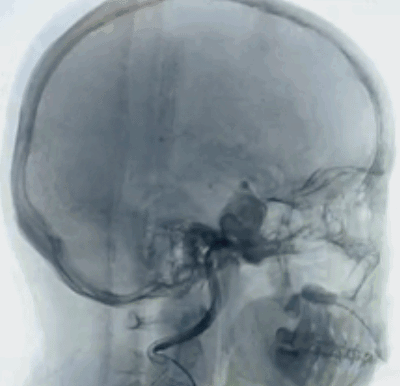

现病史:患者1个月前无明显诱因开始出现右侧眼睑下垂,伴有视力模糊,无意识障碍,无肢体活动障碍。门诊以“脑动脉瘤”收入院。术前MRA影像学检查显示:动脉瘤位于右侧颈内动脉床突段,载瘤血管直径为5.0mm,定义该动脉瘤为目标动脉瘤。

诊断结果:右侧颈内动脉床突段可见两枚囊状动脉瘤,动脉瘤大小分别为23*19mm、8.6*5.4mm。手术计划方案:右侧颈内动脉床突段动脉瘤抗凝血流导向密网支架植入术。

1、以Seldinger技术穿刺右侧股动脉成功后,留置6F股动脉鞘。6F DA导管超选至右侧颈内动脉海绵窦段,行3D造影提示:右侧颈内动脉床突段分叶状动脉瘤,载瘤动脉无严重迂曲,未见合并载瘤动脉严重狭窄,未见严重的脑血管痉挛。2、选择最佳工作角度,路图下用微导丝辅助支架0.027"微导管超选至右侧大脑中动脉,通过支架微导管释放一枚5.0*35mm抗凝血流导向密网支架(纽创医疗)。3、抗凝血流导向密网支架放置合适位置,完全覆盖瘤颈,释放后抗凝血流导向密网支架打开良好。术后造影见动脉瘤瘤体造影剂滞留明显,动脉瘤瘤颈造影剂滞留明显,靶动脉瘤Raymond Ⅲ级。